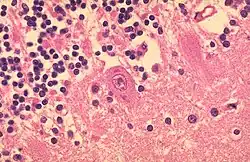

- Mehrkernige Riesenzellen - Sie entstehen durch Verschmelzung mehrerer Zellen oder bei inhibierter Zellteilung und kommen sowohl physiologisch als auch im Rahmen pathologischer Prozesse vor.

- Histiozytäre Zellen:

- Fremdkörper-Riesenzellen - Typisch in Fremdkörpergranulomen, die Zellkerne sind in einem Haufen zusammengelagert

- LANGHANS-Riesenzellen - In Tuberkulosegranulomen, die Kerne sind hufeisenförmig angeordnet

- ANITSCHKOW-Riesenzellen - Bei rheumatischer Myokarditis

- TOUTON-Riesenzelle - Schaumzellen, bei denen um eine kleine schaumfreie Insel mehrere Kerne ringförmig angeordnet sind, Vorkommen z.B. bei juveniler Xanthogranulomatose, siehe Abb.